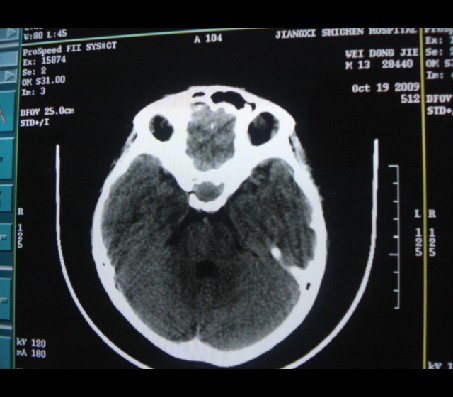

男性,12岁。反复头痛呕吐半月。脑积液无异常。病变部位ct值32hu,dwi无异常。

鞍上为主,累及鞍内,垂体受压位于鞍底。mri呈短t1、长t2信号,不太支持生殖细胞肿瘤,首考颅咽管瘤。

鞍内囊性占位性病变,t1wi、t2wi,均为高信号影。ct平扫为等密度。发病年龄较小。故首先考虑颅咽管瘤,可以做ct增强扫描